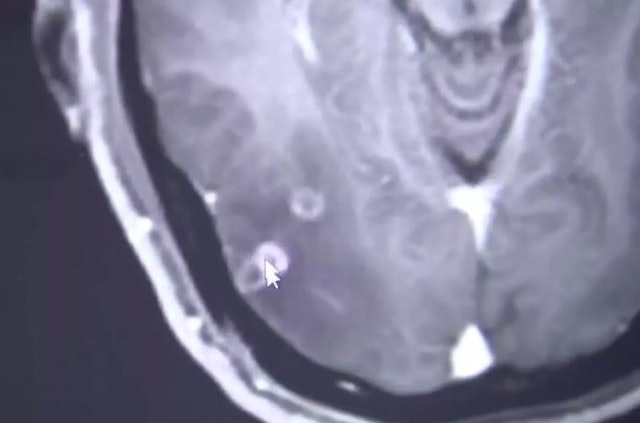

英国《镜报》报道,朱男早前吃火锅后,出现头痛和癫痫症状,持续一个月后感到困扰,决定到医院求诊。医生检查后发现,朱男体内有700多条绦虫,包括大脑、胸部和肺部,诊断是绦虫病。

朱男忆述,一个月前曾吃火锅,可能当时吃了未煮熟猪肉。医生说,绦虫感染已对患者器官“造成损害”,幸好可以泻药和药物治疗。医生提醒,日常生活中很多肉类食物,比如烤羊肉、烤猪肉,如果没有煮熟就吃,绦虫卵会在摄入时存活下来,在体力传播引起不同疾病。(香港01)